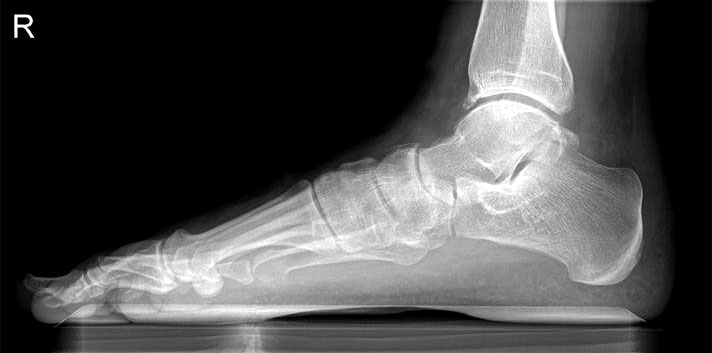

Abbildung Nr. 1: Röntgen Fuß: dp und seitlich stehend.

Es wurden insgesamt 16 Patienten nach dieser Methode operiert, sie erhielten alle das oben genannte postoperative Regime. Der durchschnittliche Nachuntersuchungszeitraum betrug 15 Monate (10-31 Monate), das Patientenalter betrug im Durchschnitt 54 Jahre (48-75 Jahre), das Geschlechtsverhältnis männlich : weiblich betrug 3 : 13. Das durchschnittliche Körpergewicht der Patienten betrug 84kg (66-98 kg). Die Auswertung erfolgte durch die VAS und den AOFAS Score, sowie an Hand der Zufriedenheit der Patienten. Desweiteren wurden die radiologischen Parameter (lateraler talonavicularer Winkel, Saltzmann-Aufnahme und talonavicularer Überdeckungswinkel) prä- und postoperativ ausgewertet sowie die Komplikationen analysiert.

Es konnte, bei präoperativer Unfähigkeit zum einbeinigen Zehenspitzenstand, beim letzten Follow up in 62% der Fälle ein schmerzloser einbeiniger Zehenspitzenstand erreicht werden. Der Saltzmann-Winkel konnte von präoperativ 11° (7-17°) auf 3° (1-8°) korrigiert werden. Der seitliche Metatarsale I Winkel wurde von 18° präoperativ (13-23°) auf 7° (5-13°) postoperativ korrigiert. Der talonaviculare Überdeckungswinkel konnte von präoperativ 10° (4-18°) auf postoperativ 7° (2-15°) reduziert werden.